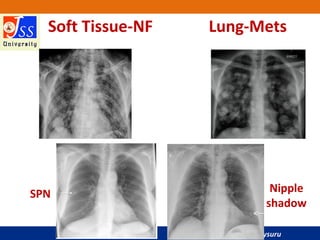

Soft Tissue-NF Lung-Mets

Nipple

shadow

SPN